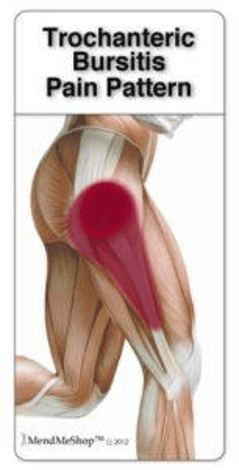

The main symptom of trochanteric bursitis is pain in the outer hip area. This pain is often worsened by putting pressure or lying on the painful hip. Furthermore, the pain will be worsened by walking, running, or any other movement of the hip. Initially, the pain may be very sharp but will lessen to more of a chronic ache. The affected leg may also show some swelling, with heat or redness near the site of the pain as a possibility.